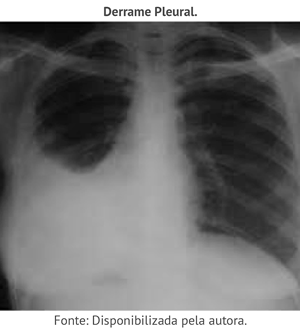

Clique nos números abaixo e observe as imagens radiológicas referentes a pneumonia TB, TB miliar e derrame pleural.